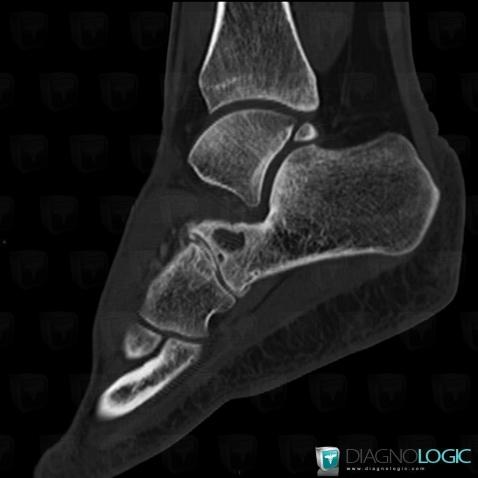

Here is the specific information in the key image above:

- Diagnosis Degenerative joint disease, Location(s) Cuboid, with gamuts Lucent lesion in foot, Sclerotic lesion in foot